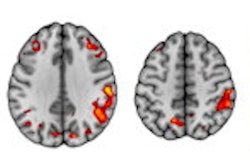

A 56-year-old man presenting with severe COVID-19. The patient had been hospitalized in the ICU for 20 days when an MRI was performed due to delayed awakening despite discontinuation of sedation. He presented with acute respiratory distress syndrome and was intubated on high-flow supplementary oxygen and placed in the prone position. 3D fluid-attenuated inversion recovery-weighted MRI reformatted in the axial plane shows several hyperintense nodules of the posterior pole of the globe located in the macular region (white arrowhead) and the extramacular region (black arrowheads). Note the presence of a focal temporal retinal detachment of the left eye (arrow). Images and caption courtesy of the RSNA.The study results highlight the need for follow-up eye health screening in patients with severe COVID-19, which could consist of imaging the eyes with high-resolution MRI; fundoscopy to assess the back of the inside of the eye; or optical coherence tomography, which visualizes the eye's structure, according to Lecler's team.